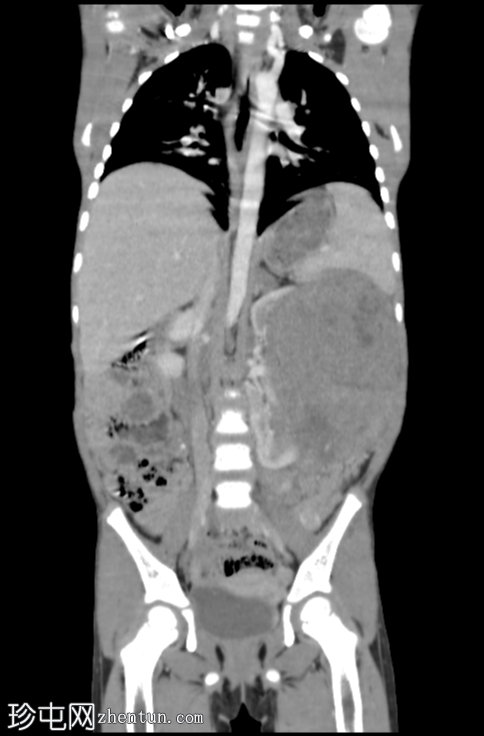

轴位增强扫描(门静脉期)

冠状位增强扫描(门静脉期)

CT扫描显示左侧腹盆腔内存在一个较大的、部分边界清晰、呈不均匀强化的软组织密度肿块。肿块后方与左肾无法分离。

肿块对邻近器官有明显的压迫作用。

右肾外观未见异常。